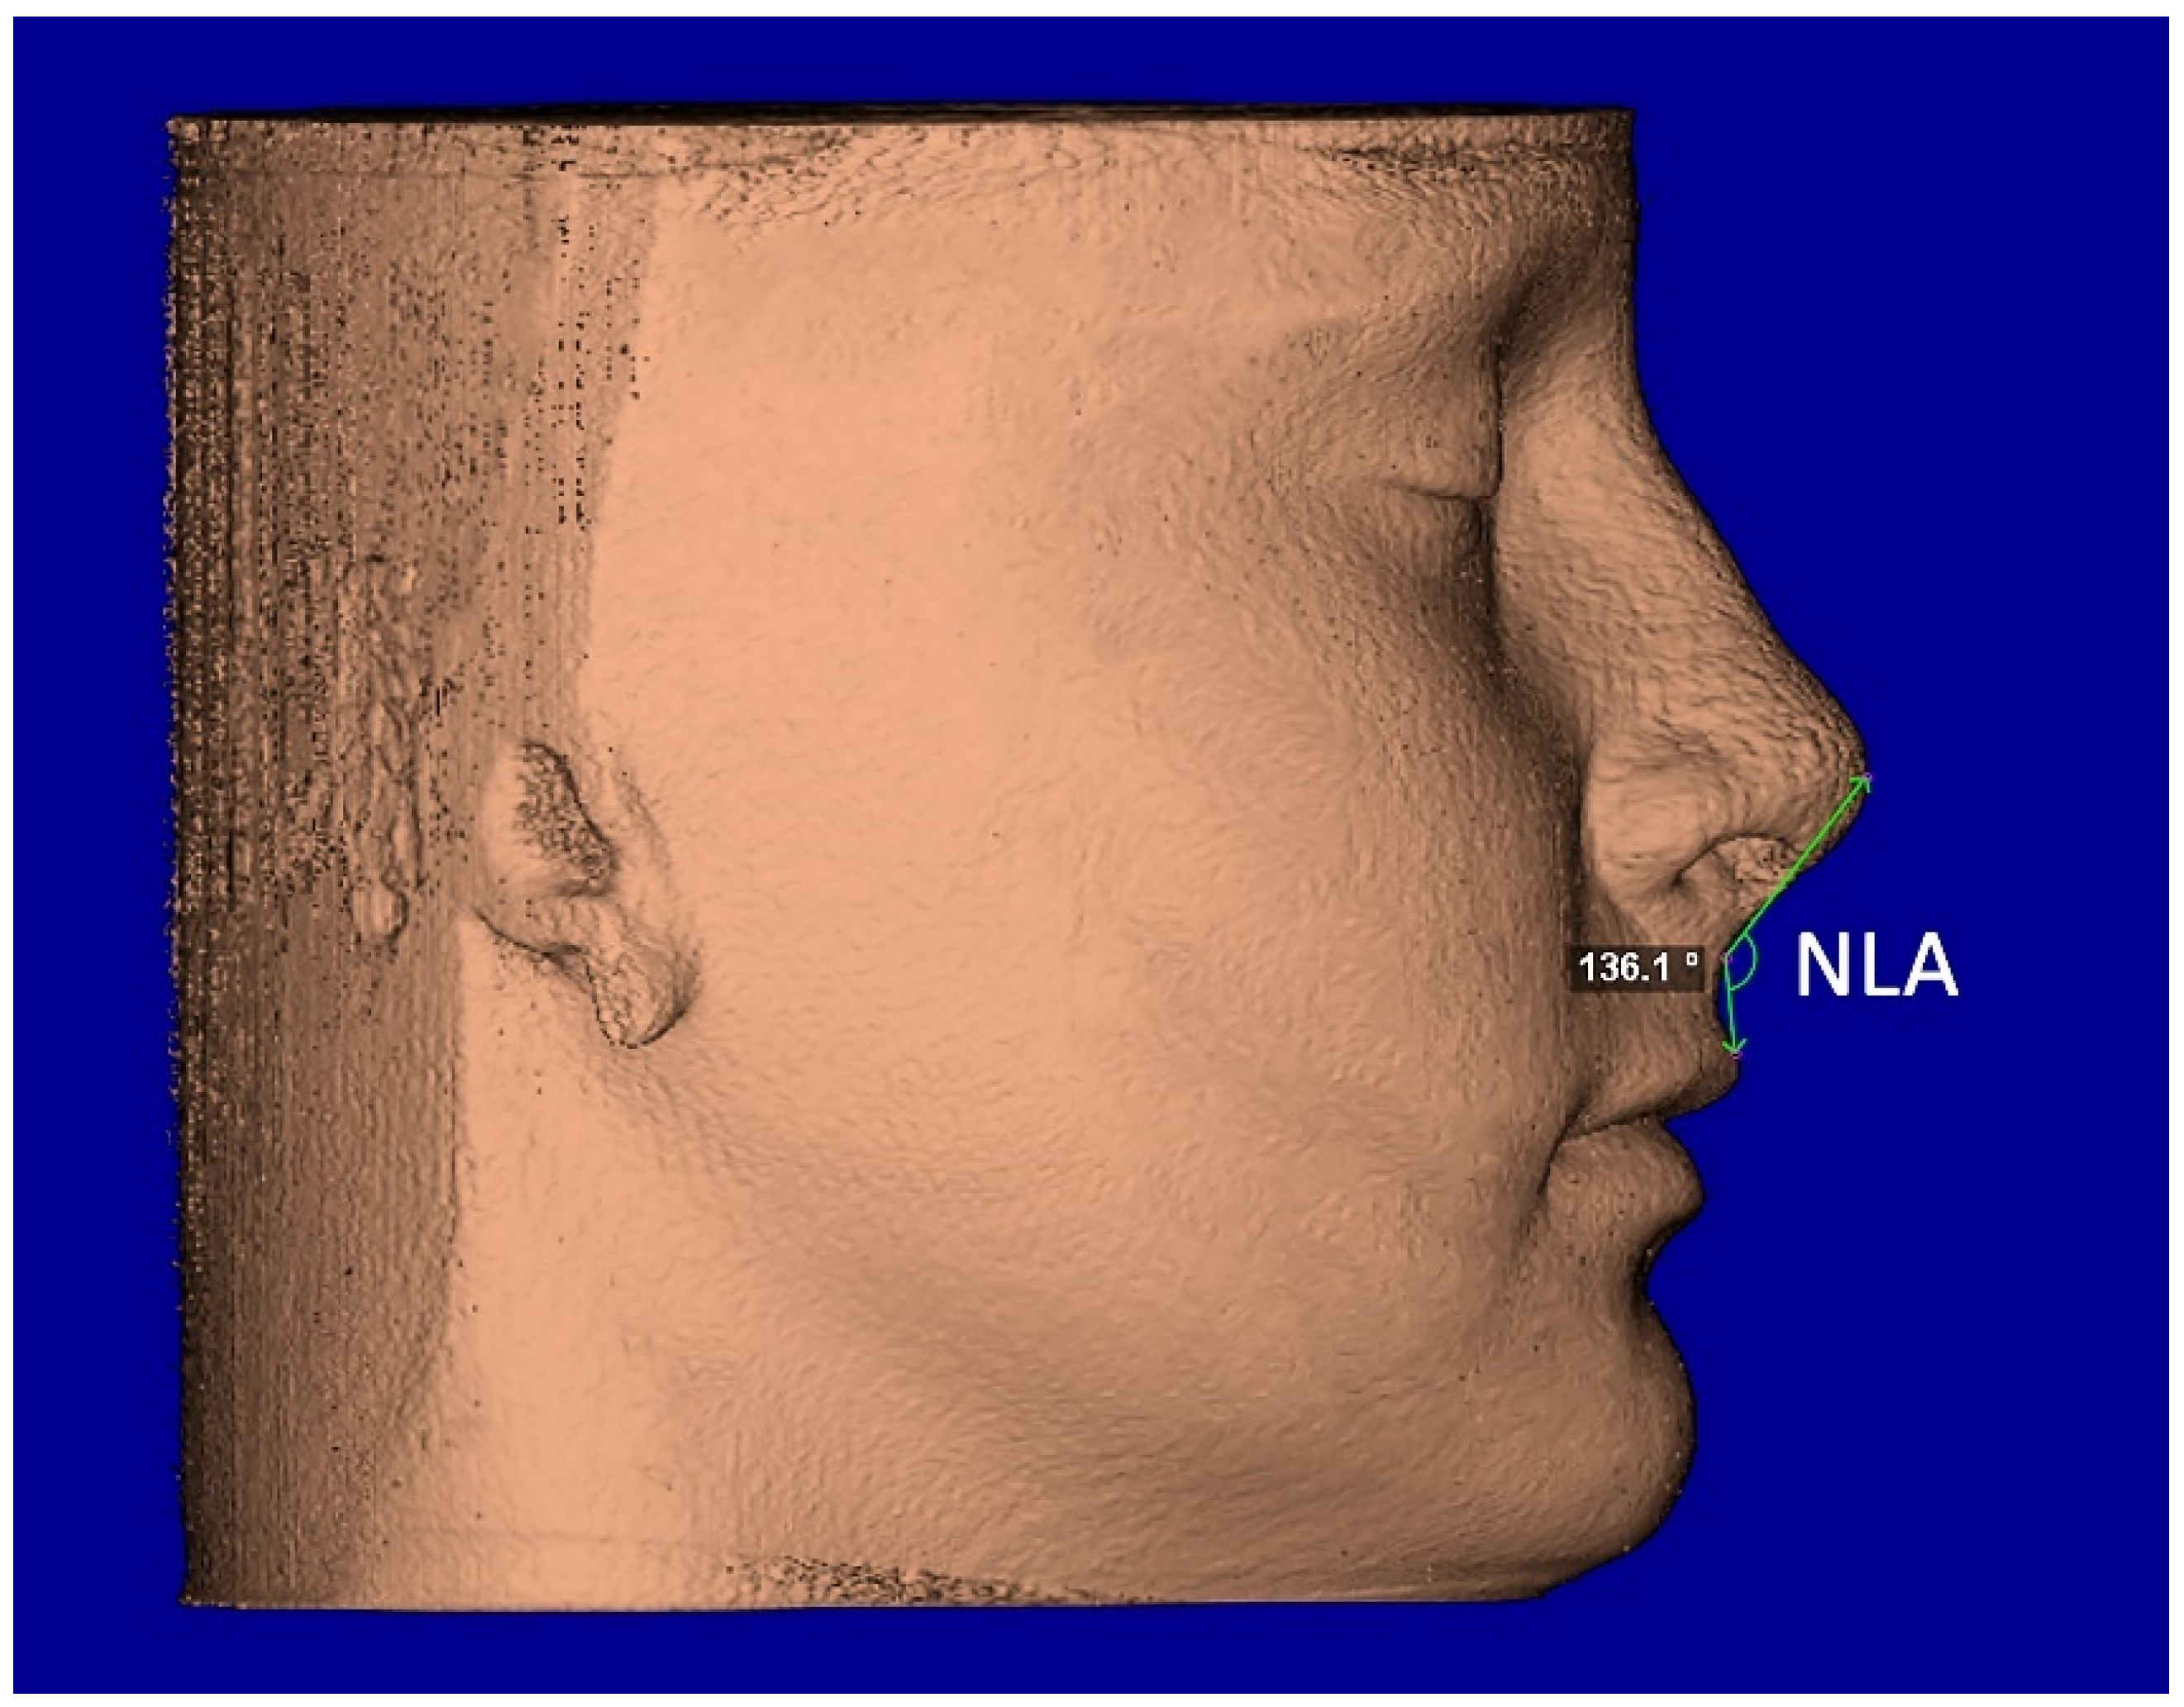

The segmentation mask of facial soft-tissue was created, setting the Hounsfield units threshold between −1024 and −200 and then converted into a 3D rendered model. The analysis of the nasal soft-tissue region was performed using the following measurements [17] (Table 1): Alar base width (ABW) (Figure 5), Alar width (AW) (Figure 5), Length of the nose (NL) (Figure 6), Length of the nasal filter (NFL) (Figure 6), Naso-labial angle (NLA) (Figure 7).

Figure 7.

Facial soft-tissue linear measurement of the naso-labial angle (NLA).

A small increment of nasal length (NL), nasal filter length (NFL), and nasolabial angle (NLA) were found in both groups between T0 and T1; instead, a small reduction in the same measurements was recorded at T2. However, these changes were not statistically significant (p > 0.05) (Table 3). Finally, no differences were found between the TB and BB groups in the changes of NL, NFL, and NLA recorded at 6 months (T0–T1) and 1 year (T0–T2) after maxillary expansion (p > 0.05) (Table 4).

4.2. Post-Retention Sagittal Changes

Another assumption of this study is the possibility that RME, in the form of TB and/or BB anchorage, can change the sagittal projection of the soft tissue in the nasal region. A small increment of nasio-labial angle, nasal filter, and nasal length was found in both TB and BB groups; however, these findings were not statistically significant as well as they did not differ between the two groups. As far as we know, the only study that looked at the height of soft tissue in the nose was that of Magnonson et al. [18]. In that study, the authors found an insignificant increase (p > 0.05) of 0.18 mm, but in contrast to our study that observed changes after RME, they were observing changes following surgical disjunction. Nevertheless, despite being not statistically significant, the increment of nasio-labial angle, nasal filter, and nasal length data were consistent and could be attributed to adaptive postural changes to accommodate the width and thickness of the expander appliance [24].